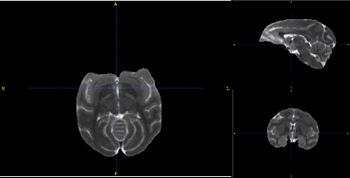

| − | Image:T2template_cr.jpg|Population Specific T2 template image | + | Image:T2template_cr.jpg|Population Specific T2 template image|right |

- Using a rhesus tissue atlas provided by the UNC Neuro Image Analysis Laboratory and the UWisc Harlow Primate Laboratory we have segmented the data into WM/GM, and CSF capartments using the Lobulated EM Segmentation method. These segmentations have been averaged to create a study-specific tissue atlas.

- Rhesus Probabilistic Atlas